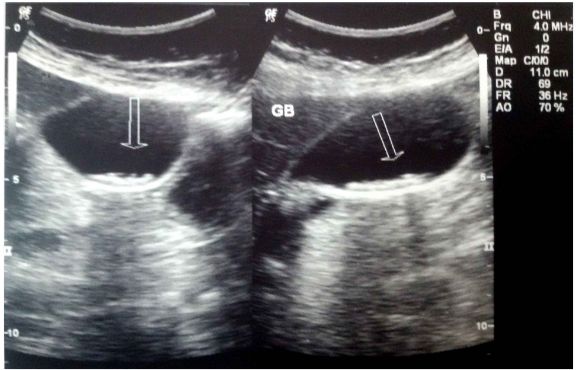

A 40-years-old non-smoker, non-alcoholic, vegetarian male presented with mild to moderate pain in right upper abdomen for 4 to 5 months. Pain was aggravated after the meal. There was history of two episodes of vomiting after attack of severe pain in last one month. He consulted to his family physician for the same complaints and took antacids and proton pump inhibitors (PPIs) but got only time being relief. Ultrasonography (USG) abdomen Figures 1 & 2 showed well distended gallbladder with normal wall thickness but sludge in the lumen. The patient was advised for the laparoscopic cholecystectomy and for the same referred to us. The patient was then thoroughly examined and nothing significant could be detected in systemic or local examination. The blood biochemistry and serology were also within normal limit except raised Aspartate transaminase (AST) 89 IU/L and Alanine aminotransferase (ALT) 142 IU/L. Patient was given OmlivTM, one tablet twice daily for 45 days. The follow-up USG (Figure 3) revealed normally distended gallbladder with normal wall thickness and clear lumen. It was concluded that the OmlivTM can clear the gallbladder sludge and is also effective for the symptomatic improvement of the patient.

Figure 1 Case No. 1 [Pre-treatment ultrasonography scan showing biliary sludge].

Figure 2 Case No. 1 [Pre-treatment ultrasonography scan showing biliary sludge].